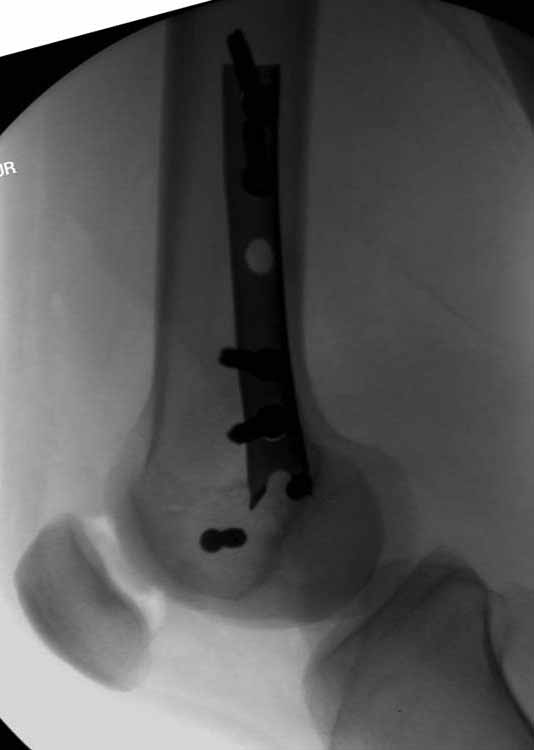

Коллеги, извиняюсь за задержку с результатом. Через медиальную артротомию обнажили н/3 бедра, отрепонировали внутренний мыщелок, затем по нему сопоставили суставную поверхность бедра с латеральным мыщелком.

Больная выписана в ортезе с регулируемым углом сгибания в колене, с рекомендациями через 3 нед. удалить спицы и начать разрабатывать сустав.

По прямому снимку репозиция удалось, поздравляю! А с латеральной стороны подозрение на флексионный компонент латерального мыщелка остается, а снимок получился косым, надо было бы повторить.

Выбор имплантов не совсем удачный, подкожно выступающие болты в мыщелках вскоре могут привести к проблемам. Вместо солитарной фиксации болтом-стяжкой дистально можно было бы добавить пару винтов, которые создали бы ротационную стабильность и межфрагментарную компрессию.

Возможно, есть скрытый замысел, неочевидный для нас - не понятны латерально оставленные спицы. Спицы возможный очаг вторичного осложнения, и, тем более у взрослых, тонкие спицы не создают адекватную фиксацию.